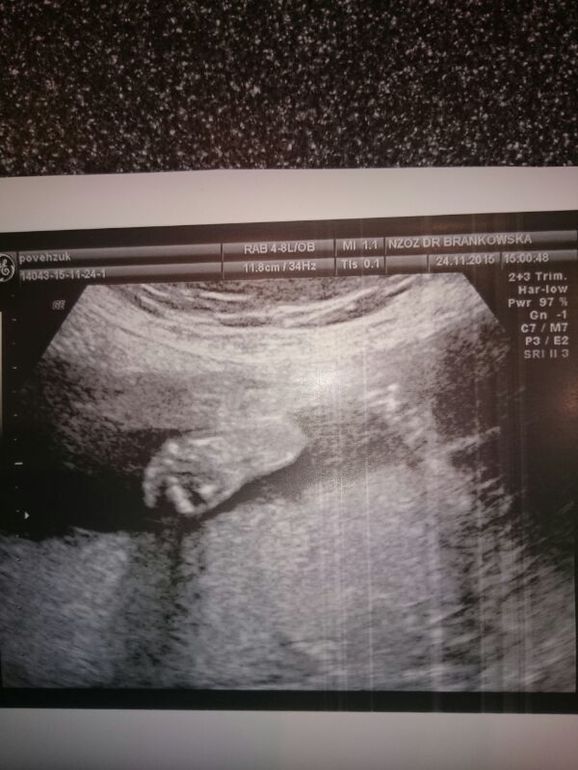

Теперь фотографии

И фото как закрывалась рученьками)))